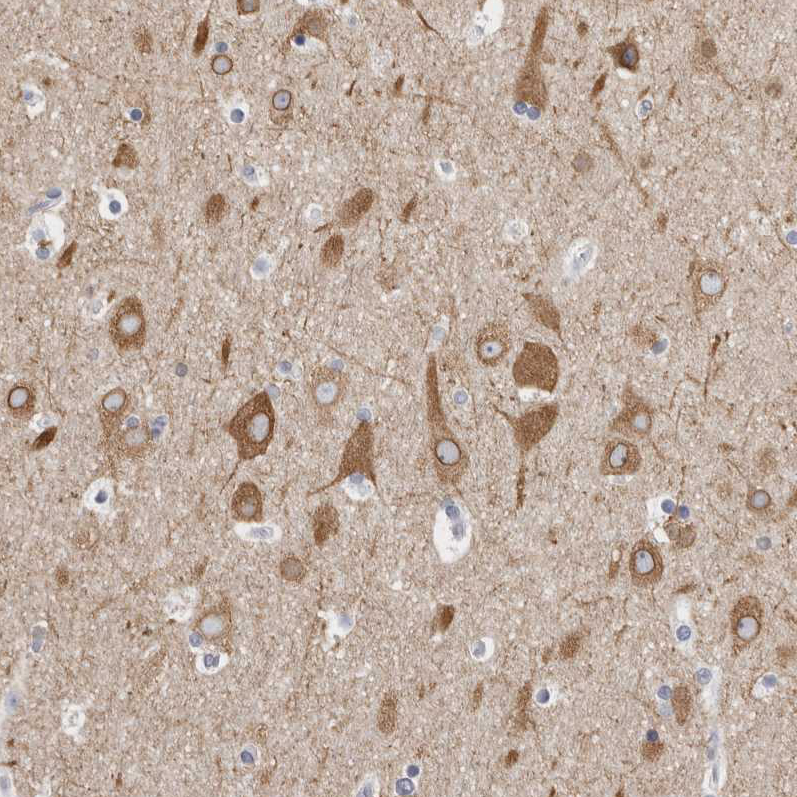

Immunohistochemical staining of human cerebral cortex shows moderate cytoplasmic and membranous positivity in neurons.